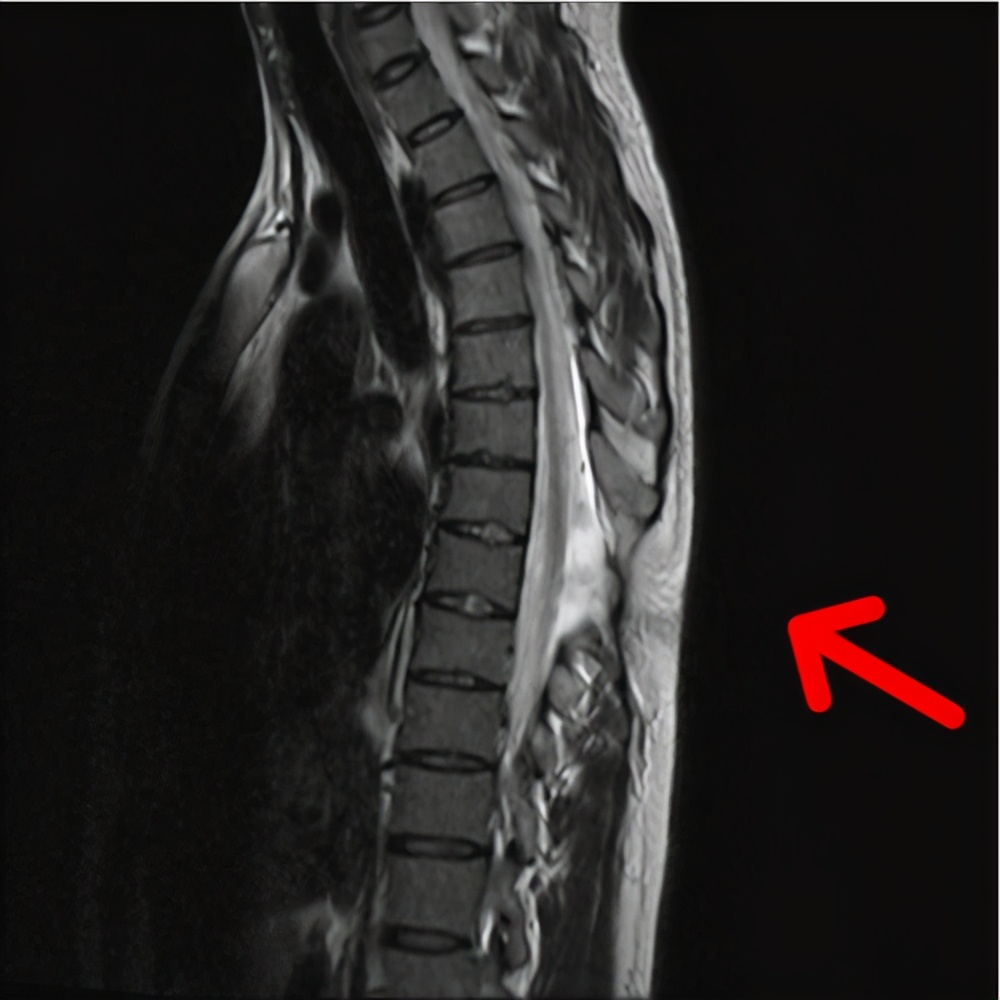

高弓足一般与先天发育有关系,如果发现高弓足,常规的需要拍腰椎片子,看腰椎有没有先天的发育异常,像隐形脊柱裂发育异常会出现高弓足。